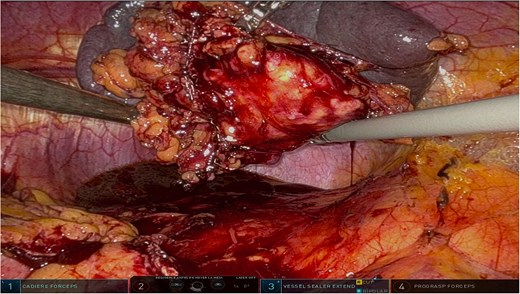

The surgery was performed using the Da Vinci robotic system under general anesthesia. The patient was positioned supine with reverse Trendelenburg. Four robotic trocars and one assistant trocar were placed. The gastro-splenic ligament was dissected to expose the distal pancreas, and the pancreas was transected using a linear stapler, ensuring tumor-free margins (Fig. 2). The splenic artery and vein were individually ligated with robotic sutures, and the spleen was mobilized and removed along with the pancreas (Fig. 3). The specimen was extracted via mini-laparotomy and sent for histopathological analysis (Fig. 4).

Intraoperative image highlighting the robotic ligation of the splenic artery. The Da Vinci system facilitated precise dissection and secure vascular control, minimizing blood loss and ensuring the preservation of adjacent structures, such as the splenic vein. This step was critical for the safe resection of the distal pancreas and spleen.